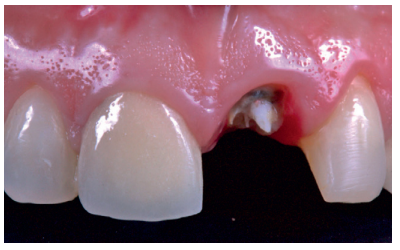

Se presenta el caso clínico de una mujer de 52 años de edad, que acudió a la consulta odontológica debido al descementado de una corona metal-cerámica dentosoportada en el diente 2.1 (ICSI) (Figuras 1-3). La paciente refería una alta preocupación por su estética.

Exploración

La paciente refería dolor a la masticación en el sector anterosuperior, localizado en la zona del ICSI, el cual desaparecía con la toma de fármacos analgésicos. En la exploración clínica intraoral se observó que la corona descementada conservaba restos del muñón del ICSI, así como un perno colado que servía como andamiaje de la restauración. El ICSI se trataba de un resto radicular, con pérdida total de la estructura dentaria y sin un ferrule que pudiese asegurar una nueva rehabilitación predecible9 . La paciente presentaba una línea de sonrisa media y un fenotipo gingival fino, el cual se acompañaba de recesión gingival en el diente afectado, así como en dientes contiguos del segundo cuadrante. Presentaba palpación, percusión y test de mordida positivo y vitalidad negativa en el ICSI, sin presencia de bolsa periodontal (profundidad de sondaje ≤ 3mm) ni movilidad. Se llevó a cabo una exploración radiológica complementaria, que incluyó una radiografía periapical y la realización de una tomografía computarizada de haz cónico (CBCT) (Figura 4). Tras la valoración de dichas pruebas, se observó la presencia de una fractura coronaria horizontal completa subgingival sin afectación ósea periapical.

Tras la exploración con las diferentes pruebas complementarias, se determinó como imposible el pronóstico restaurador del ICSI. Debido a las características clínicas del caso, y con la conformidad por parte de la paciente, el plan de tratamiento fue la realización de la exodoncia del ICSI y la colocación simultánea de un implante dental osteointegrado (IOI), asociado a una prótesis provisional implantorretenida. El hueso residual apical era favorable para colocar el IOI, tratándose de un alvéolo Clase I según Kan10, y con una integridad prácticamente total de la tabla vestibular, siendo un alvéolo tipo I según Elian11.